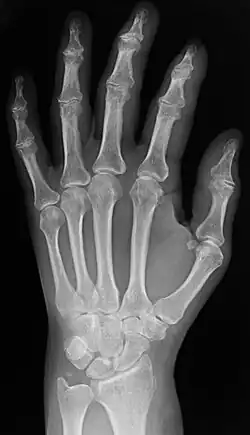

Plain X-ray of the wrist and hand

Two forms of radiographic images are in use in medical imaging. Projection radiography and fluoroscopy, with the latter being useful for catheter guidance. These 2D techniques are still in wide use despite the advance of 3D tomography due to the low cost, high resolution, and depending on the application, lower radiation dosages with 2D technique. This imaging modality uses a wide beam of X-rays for image acquisition and is the first imaging technique available in modern medicine.

• Projectional radiographs, more commonly known as X-rays, are often used to determine the type and extent of a fracture as well as for detecting pathological changes in the lungs. With the use of radio-opaque contrast media, such as barium, they can also be used to visualize the structure of the stomach and intestines – this can help diagnose ulcers or certain types of colon cancer.